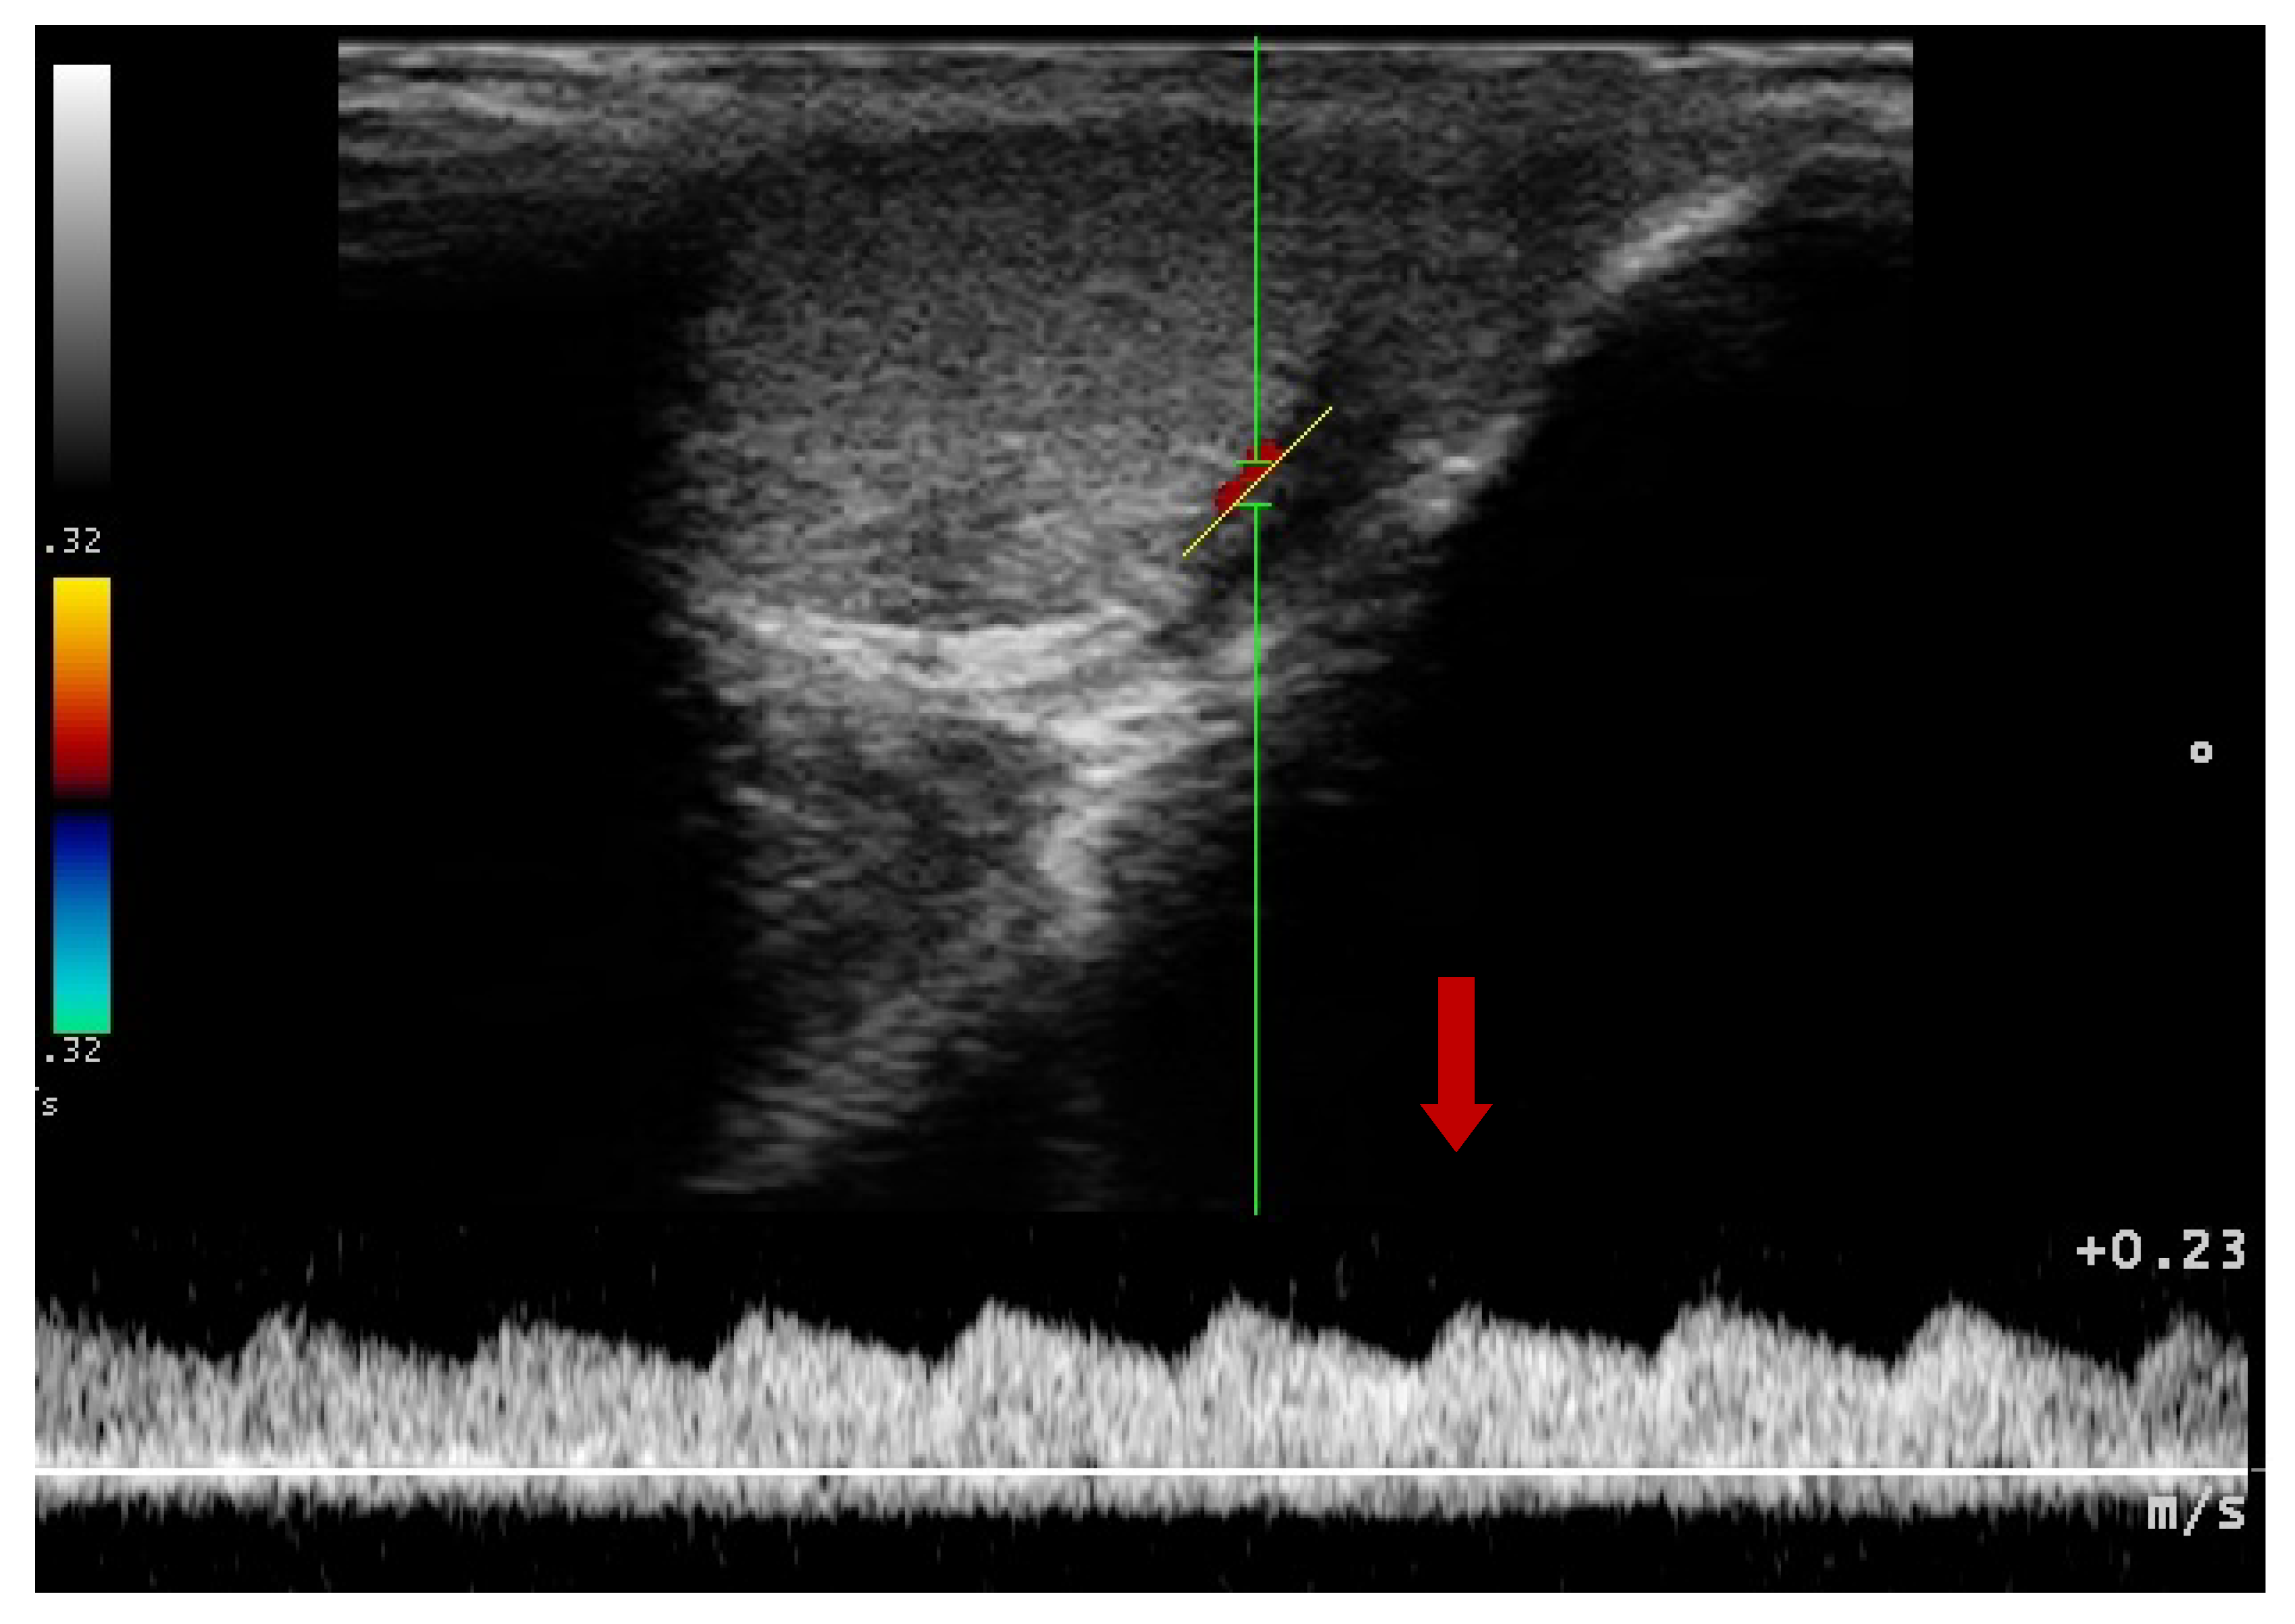

3.4. Doppler Ultrasonography of the Testicular Artery

2.6. Doppler Ultrasonography—Testes